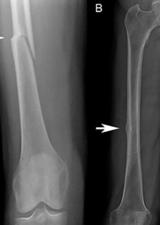

Researcher studies rare fractures in post-menopausal women

Researchers in the Faculty of Kinesiology and the McCaig Institute for Bone and Joint Health are studying the cause of these fatigue fractures, known as atypical femoral fractures that occur in the thighbone, to help prevent this injury.